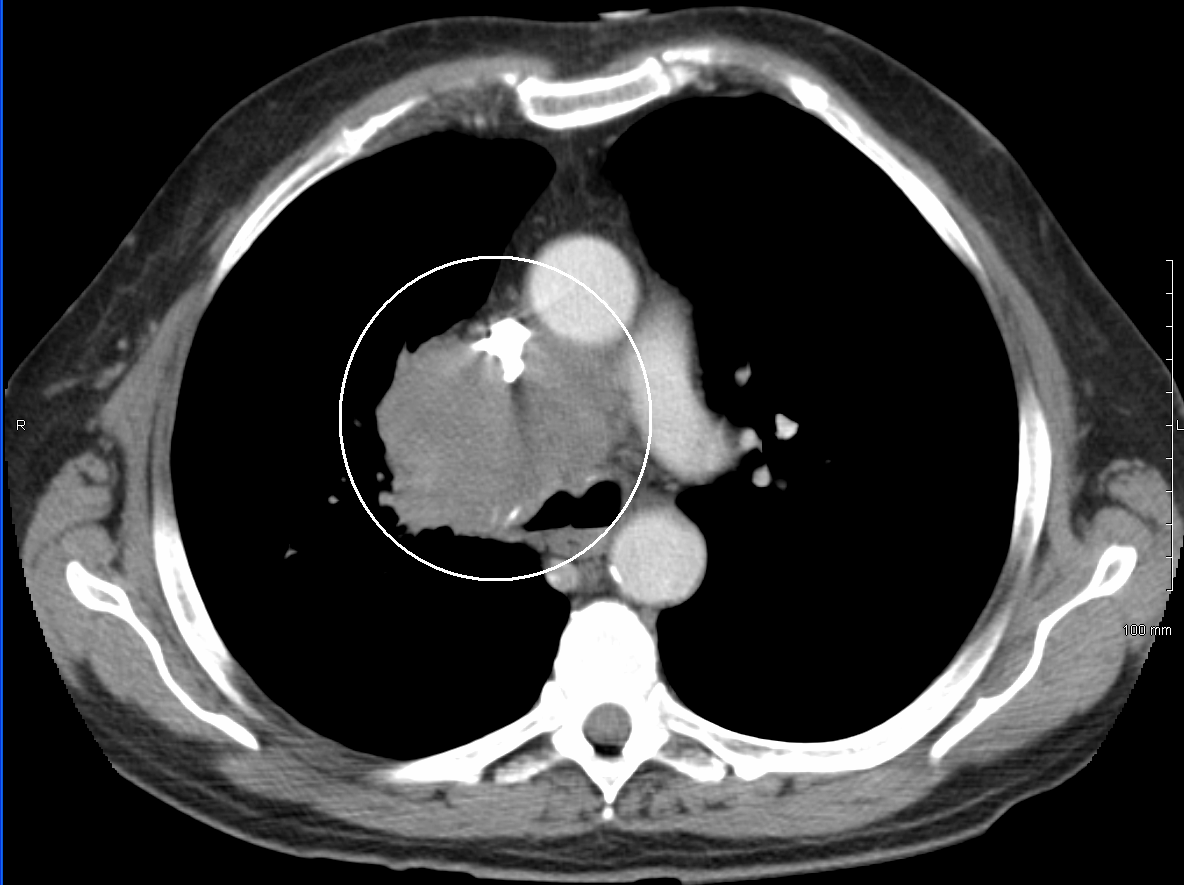

상대정맥 증후군(SVCS)을 진단하는 주요 기술에는 흉부 X-레이, CT 스캔, 기관지 내시경 검사 시 경기관지 바늘 흡인 및 종격동경 검사가 있다.[7] 흉부 X-레이는 종격동 확장을 보여줄 수 있으며, 상대정맥 증후군의 주된 원인을 나타낼 수 있다.[7] 그러나 상대정맥 증후군 환자의 16%는 정상적인 흉부 X-레이 소견을 보인다. CT 스캔은 조영 증강을 해야 하며, 목, 가슴, 하복부 및 골반에 대해 촬영해야 한다.[7] CT 스캔은 또한 근본적인 원인과 질병의 진행 정도를 보여줄 수 있다.[7]